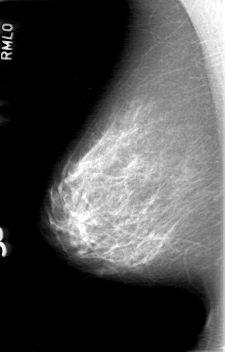

D_4058_1.RIGHT_CC

RIGHT_CC LINES 5251 PIXELS_PER_LINE 3136 BITS_PER_PIXEL 12 RESOLUTION 43.5 NON_OVERLAY